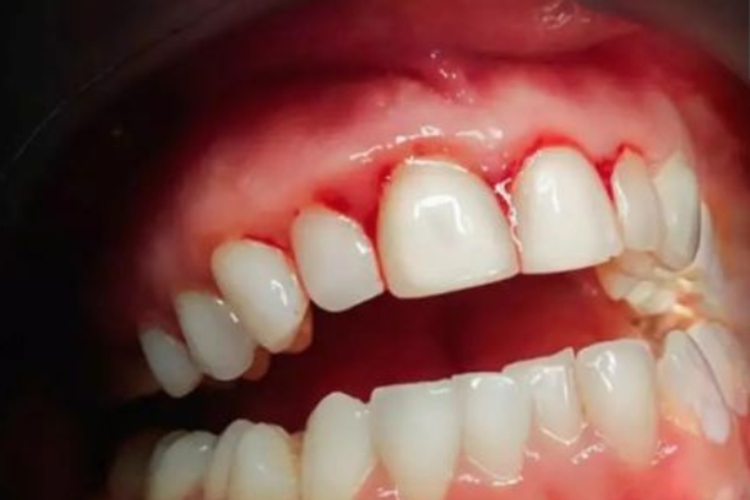

皮肤黏膜出血:表现为牙龈肿胀、出血,并可因牙龈及齿槽坏死而致牙齿松动、脱落;皮肤可出现瘀点、瘀斑、毛囊过度角化、周围出血,并可出现鼻出血、血尿、便血、关节出血、颅内出血等症状。